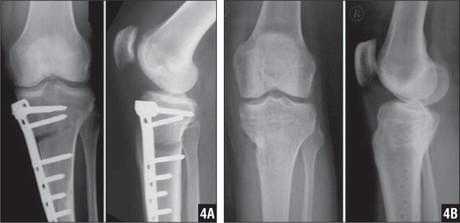

Спицами Киршнера в основном фиксируют мелкие кости и суставы (пальцы стопы и кисти, плюсневые и пястные кости). Иммобилизация проводится, как правило, в течение 4-6 недель после операции. Факсация может быть как наружной, т.е. конец спицы находится над поверхностью кожи, так и внутренней, т.е. спица полностью погружена под кожу для снижения риска инфицирования и неудобств пациента. Исполюзуется для временной фиксации. Так же существует погружной остеосинтез спицами и проволокой для остеосинтеза более крупных костей по Веберу, например, при:

Удаление спиц и проволоки после остеосинтеза надколенника по Веберу

При переломах надколенника (коленной чашечки) со смещением отломков выполняется операция остеосинтеза, т.е. скрепление костных фрагментов для восстановления целостности кости и соответственно функции коленного сустава. Так как при отказе от операции пациент рискует остаться инвалидом.

Для остеосинтеза надколенника в подавляющем большинстве случаев используется методика Вебера. Когда костные отломки скрепляются двумя титановыми спицами Киршнера и дополнительно стягиваются титановой проволокой 8 образно. Это позволяет быстро и очень эффективно восстановить поврежденную кость и что немаловажно металлоконструкция минимальна по стоимости. Но у нее есть один большой минус. Очень часто пациенты испытывают дискомфорт и боль в области мпиц и проволоки, так как она находится правктичекски сразу под кожей. Поэтому часто выполняется удаление металлоконструкции из надколенника.

После того как кость срослась и металлоконструкция выполнила свою функцию ее можно удалить. Полное сращение кости происходит за 6- 8 месяцев, в некоторых случая 1 год. Именно спустя этот срок можно удалять металл.

Перед данной операцией нужно выполнить стандартные анализы крови; список можно посмотреть здесь.

Операция зачастую выполняется в условиях дневного стационара, т.е. через несколько часов после операции пациент может уйти домой. Анестезия местная, проводниковая либо наркоз. Непосредственно сама операция по времени занимает 30 минут. Найти проволку и спицы, как правило, не представляет труда для хирурга. После того как металлоконструкция удалена проводится зашивание раны и наложение асептической повязки. Пациент приходит на перевязки в первые сутки, далее можно перевязываться самостоятельно либо в лечебном учреждении рядом с домом. Швы необходимо снять через 14 дней после операции. В раннем послеоперационном периоде назначаются обезболивающие и антибактериальные препараты.

Примерно через 1 месяц после операции по удалению металлоконструкции из надколенника можно постепенно увеличивать нагрузку и возвращаться в свой обычный ритм жизни.